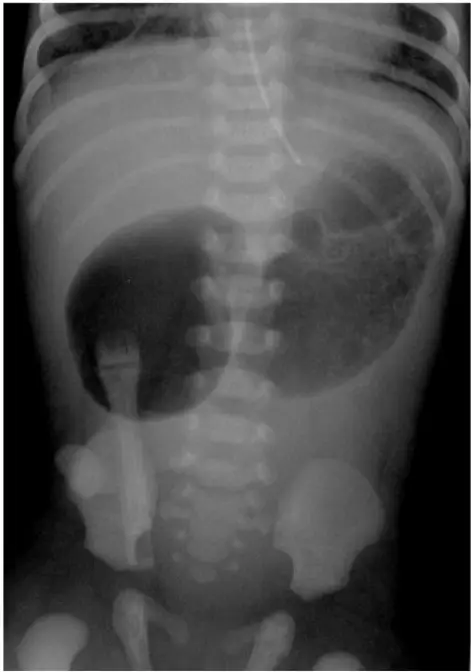

Esophageal Atresia X-ray: Radiographic Signs:

Esophageal Atresia X-ray: Other Cases: Radiological cases of Surgery It is a congenital condition that can be identified through radiographic findings. Key indicators include: What is Esophageal Atresia? It is a birth defect where a baby’s esophagus (food pipe) doesn’t connect properly to the stomach. Instead, it ends in a pouch, making swallowing impossible. This condition occurs […]